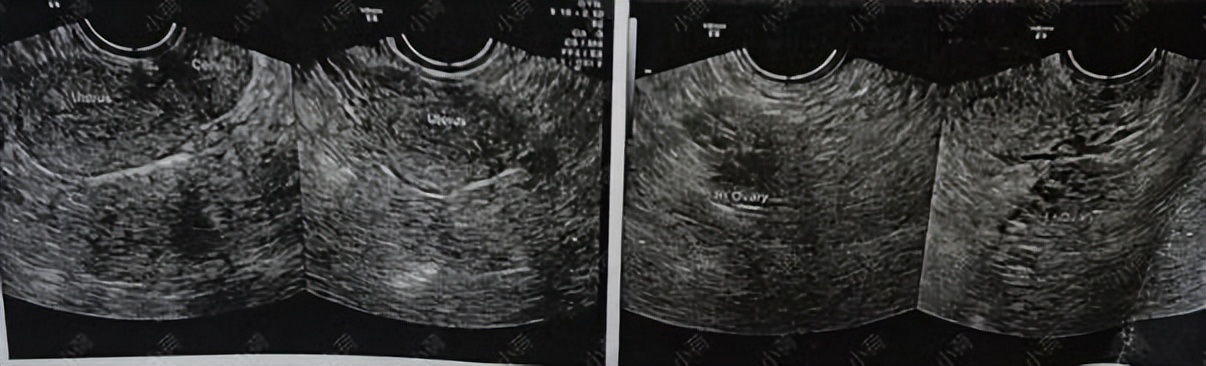

了解她的情况之后我让她去化验血,检查一下激素六项+β人绒毛膜促性腺激素,以排除怀孕;再做一个经阴道B超。

结果显示: 多囊卵巢综合征,激素紊乱

图片来源 :讲述者提供